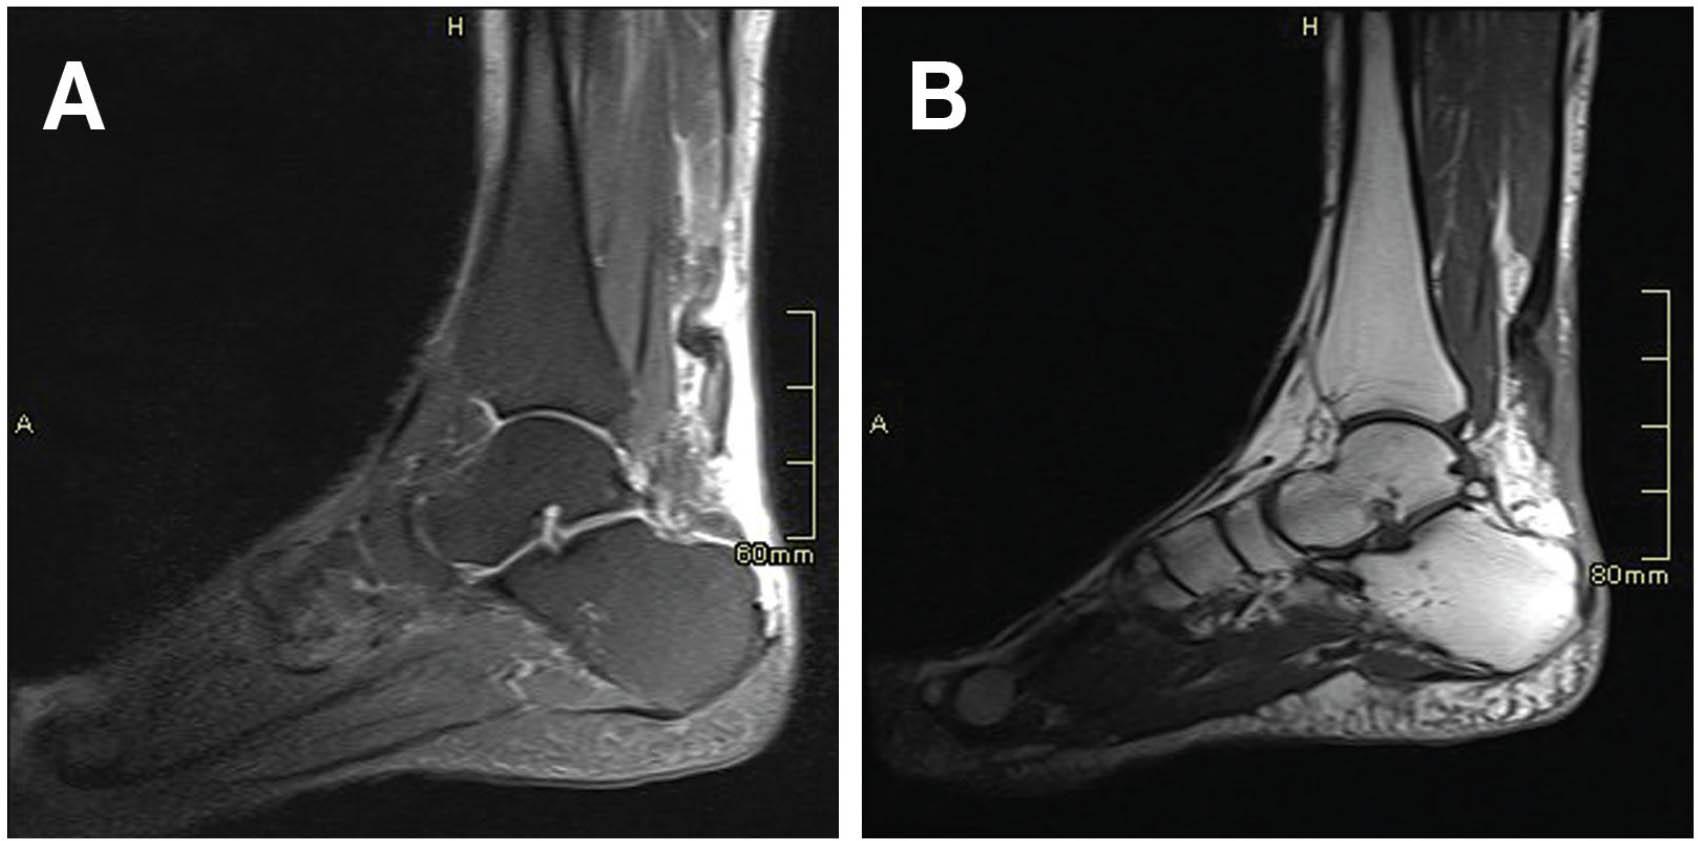

Physical examination revealed a palpable defect over the left Achilles tendon at its insertion. Absence of plantarflexion was observed using a Simmonds–Thompson test. Lumbosacral computed tomography (CT) showed diffuse degenerative changes of the spine (Figure 3). Magnetic resonance imaging (MRI) revealed that the tendinous insertion of the Achilles tendon into the calcaneus tuberosity was completely disrupted with retraction of the proximal part (Figure 4). Surgical exploration through the medial incision to the Achilles tendon down to its insertion site revealed a complete disruption of the tendon at its attachment to calcaneus with fragile, black deposited frayed edges (Figure 5A). The black pigmentation was extensive and reaching the calcaneal tuberosity, extending about 7 cm from the insertion. The excision involved the entire pigmented segment (Figure 5B) and specimens of the fragmented tendon were sent for histopathology with the suspicion of ochronosis. Tendon advancement was not possible due to the large gap created after the excision (>5 cm). A decision was taken to graft the flexor hallucis longus (FHL) tendon (Figures 5C–E). The posterior aspect of the calcaneus was involved in the deposition as well; so, it was challenging to find a healthy area to implant the graft. A suitable area 2 cm anterior to the insertion was prepared after curettage to assure a healthy vascularized bed for the graft. The FHL tendon was forfeited at the Henry knot, and the graft was pulled up through the original incision. With appropriate orientation of the fibers of the FHL tendon, the graft was secured with a conventional screw into the calcaneus. The graft was sufficiently long enough to be sutured over the proximal stump of the Achilles using an absorbable polyglactin 910 suture (Vicryl; Ethicon/Johnson and Johnson). Intraoperatively, a stable plantar and dorsiflexion of the ankle was achieved (Figure 6). Histopathological examination of the resected portion of the tendon revealed a thick fibrosed tendinous tissue with chronic inflammation and focal pigment deposition consistent with the classical features usually seen in alkaptonuria.

Figure 4

Sagittal fat saturated proton density-weighted (A) and sagittal T1-weighted (B) magnetic resonance images showing an insertional type of Achilles tendon rupture. There is discontinuity and retraction of the Achilles tendon. The tendinous insertion into the calcaneus tuberosity is completely disrupted.